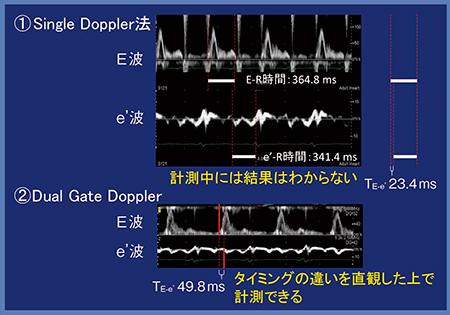

Single Doppler法にてTE-e’を測定するに当たっては,まずE波からR波までの時間(E-R時間)を測定し,続いてe’波からR波までの時間(e’-R時間)を測定して,これを差分することでようやくTE-e’が求められる(図3 (1))。しかし,E-R時間とe’-R時間を別々に測定するため,結果は計測中にはわからない。一方,Dual Gate Dopplerでは計測中に一目で確認することができる(図3 (2))。タイミングの違いを直観した上でTE-e’を測定できるので,値に自信が持てる。EFを計測する時にEye ball EFと極端にずれないか確認するのと同様である。また,図3 (2)のように,E波の方がe’波よりも速いことが一目で確信できることも大きなメリットである。

図3 Single Doppler法とDual Gate DopplerによるTE-e’測定の比較(症例1)